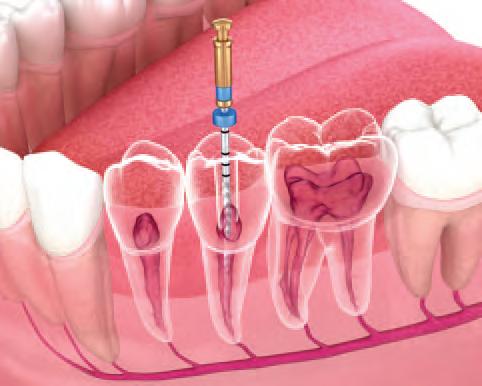

Hands-on endodontic course in Limerick

A full-day hands-on course in endodontics will be given by specialist Dr Eoin Mullane on Friday, September 20, in Limerick. This course proved very popular in 2023 when we last ran it. Thank you to Eoin for providing the course and to NSK and Coltene for supporting this programme.

On Thursday, delegates had the opportunity to avail of hands-on learning from expert practitioners at the pre-Conference courses. Dr Bob Philpott showed how to get the best results during root canal treatment, while Dr Dipesh Parmar gave an anterior composite masterclass. Drs Mairead Browne, Paul Kielty and Sarah Kate Quinlivan facilitated a deep dive into the world of botulinum toxin treatments, and Dr Seamus Sharkey brought the focus to preparation design in fixed prosthodontics. Prof. Paul Brady and Dr Catherine Gallagher offered a short refresher course on conscious sedation, and Dr Linda Greenwall gave a workshop on whitening and white spot eradication with ICON. Feedback from the courses was excellent, with delegates delighted with the range and quality of the hands-on learning on offer.